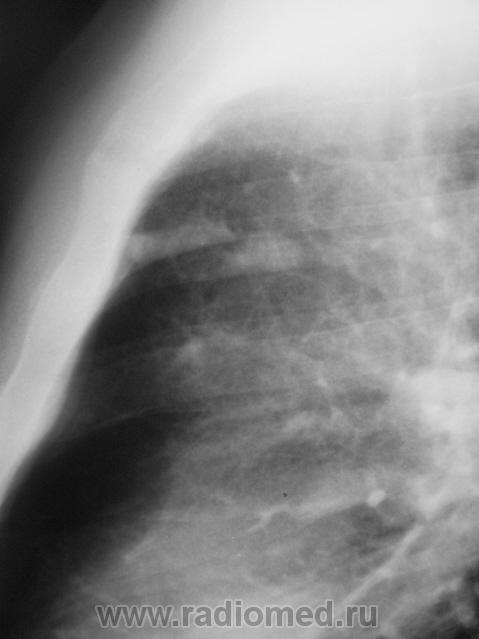

Пациент взят на контроль после проведения профилактической флюорографии.

а в легких изменения?очаговые тени в легких и склеротические изменения тела толкают на мысли о метастатическом поражении.

Мы тоже высказали мнение о наличии метастазов. У пациента установлен ( в области) рак предстательной железы, диагноз в ООД вверифицирован.